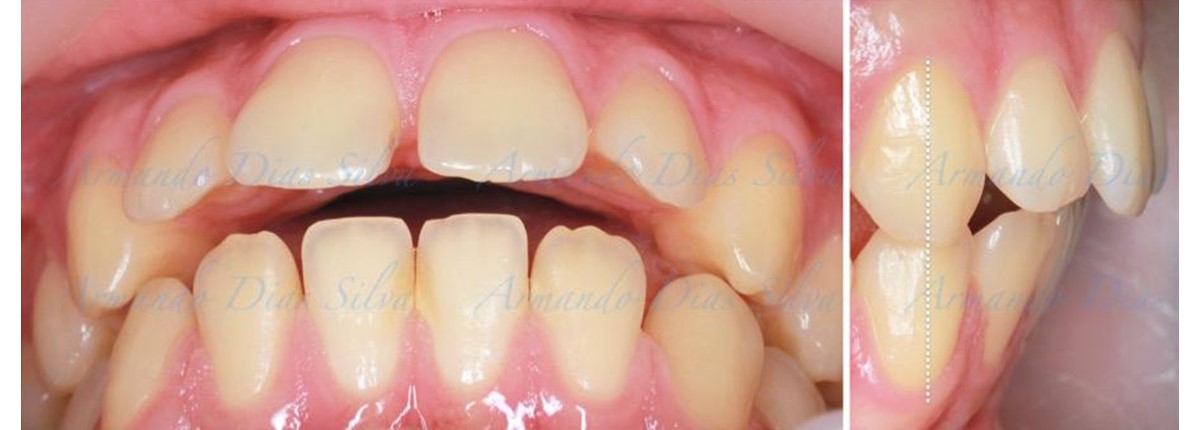

Este paciente adolescente presenta molares de Clase II y no le gusta su mordida abierta ni lo protrusivos que son sus dientes frontales. Por sus fotografías faciales, parece que su mandíbula es retrognática o le falta volumen en la barbilla. El historial del paciente también indica que existe un problema funcional al no haber guía de los incisivos.

• Molares de clase II

• Diastema

• El primer molar superior derecho está en una posición más mesial que el primer molar superior izquierdo

• Incisivos superiores e inferiores proclinados

• Orientación canina desfavorable

• Molares de clase I logrados con distalización y sin elásticos